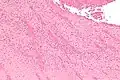

A recent pulmonary thrombo-embolus with prominent lines of Zahn. The pale areas consist of fibrin and platelets. The red areas consist of erythrocytes. | |

Lines of Zahn are a characteristic of thrombi. They have layers, with lighter layers of platelets and fibrin, and darker layers of red blood cells. They are more present on thrombi formed with faster blood flow, more so on thrombi from the heart and aorta. They are only seen on thrombi formed before death. They are named after German–Swiss pathologist Friedrich Wilhelm Zahn.

Lines of Zahn are a characteristic of thrombi.[1] They have visible and microscopic alternating layers (laminations).[2][3] Platelets mixed with fibrin form lighter layers.[2] Red blood cells form darker layers.[2] Sometimes, the term "lines of Zahn" only refers to the lighter layers.[4]

Lines of Zahn can be used to confirm diagnosis of a thrombus.[1] Their presence implies thrombosis at a site of rapid blood flow that happened before death. They are more common in thrombi formed in the heart or aorta.[5] In veins or smaller arteries, where flow is not as constant, they occur less frequently.[5] They are also only seen on thrombi formed when blood is flowing. This is a distinguishing marker between thrombi that formed before death and after death.